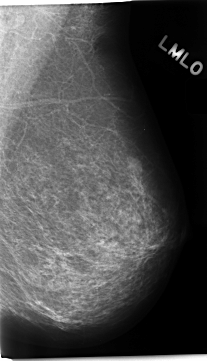

C_0230_1.LEFT_MLO

LEFT_MLO LINES 4688 PIXELS_PER_LINE 2680 BITS_PER_PIXEL 12 RESOLUTION 50 NON_OVERLAY